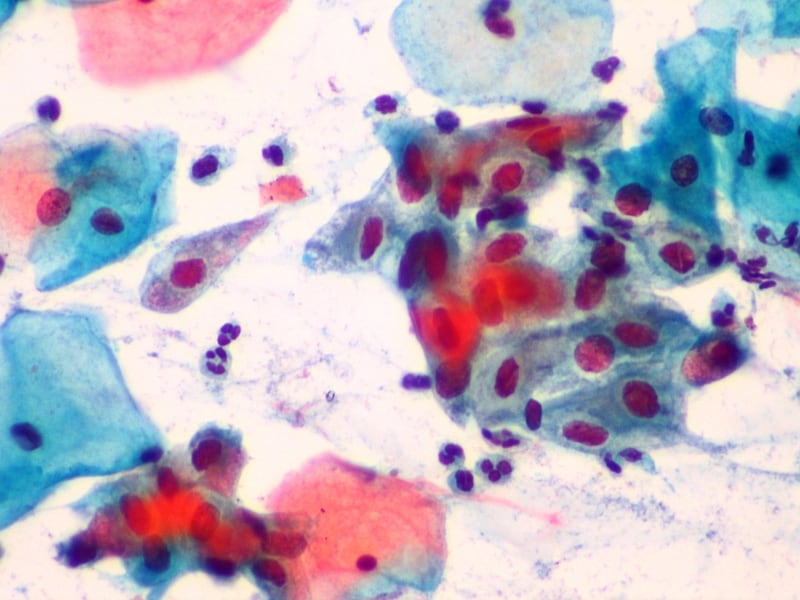

Odebrané buňky jsou natřeny na sklo a zafixovány alkoholovým roztokem. Nedílnou součástí stěru je i dobře vyplněná průvodka k vyšetření, obsahující informace o datu posledního menstruačního krvácení, užívání antikoncepce či délce trvání těhotenství. Fixovaný preparát cytologického stěru je s dokumentací odeslán k vyhodnocení do cytologické laboratoře, kde odborník-cytolog vyšetří a nález se podrobně popíše. K hodnocení je aktuálně v České republice využívána cytologická klasifikace přijatá v USA ve městě Bethesda v roce 2001.

Po velmi podrobném a jednoznačném popisu následuje doporučení dalšího postupu. Cytolog zhodnotí kvalitu stěru, hormonální stav ženy a případnou infekci a zařadí pozorované buňky děložního hrdla do příslušné kategorie.